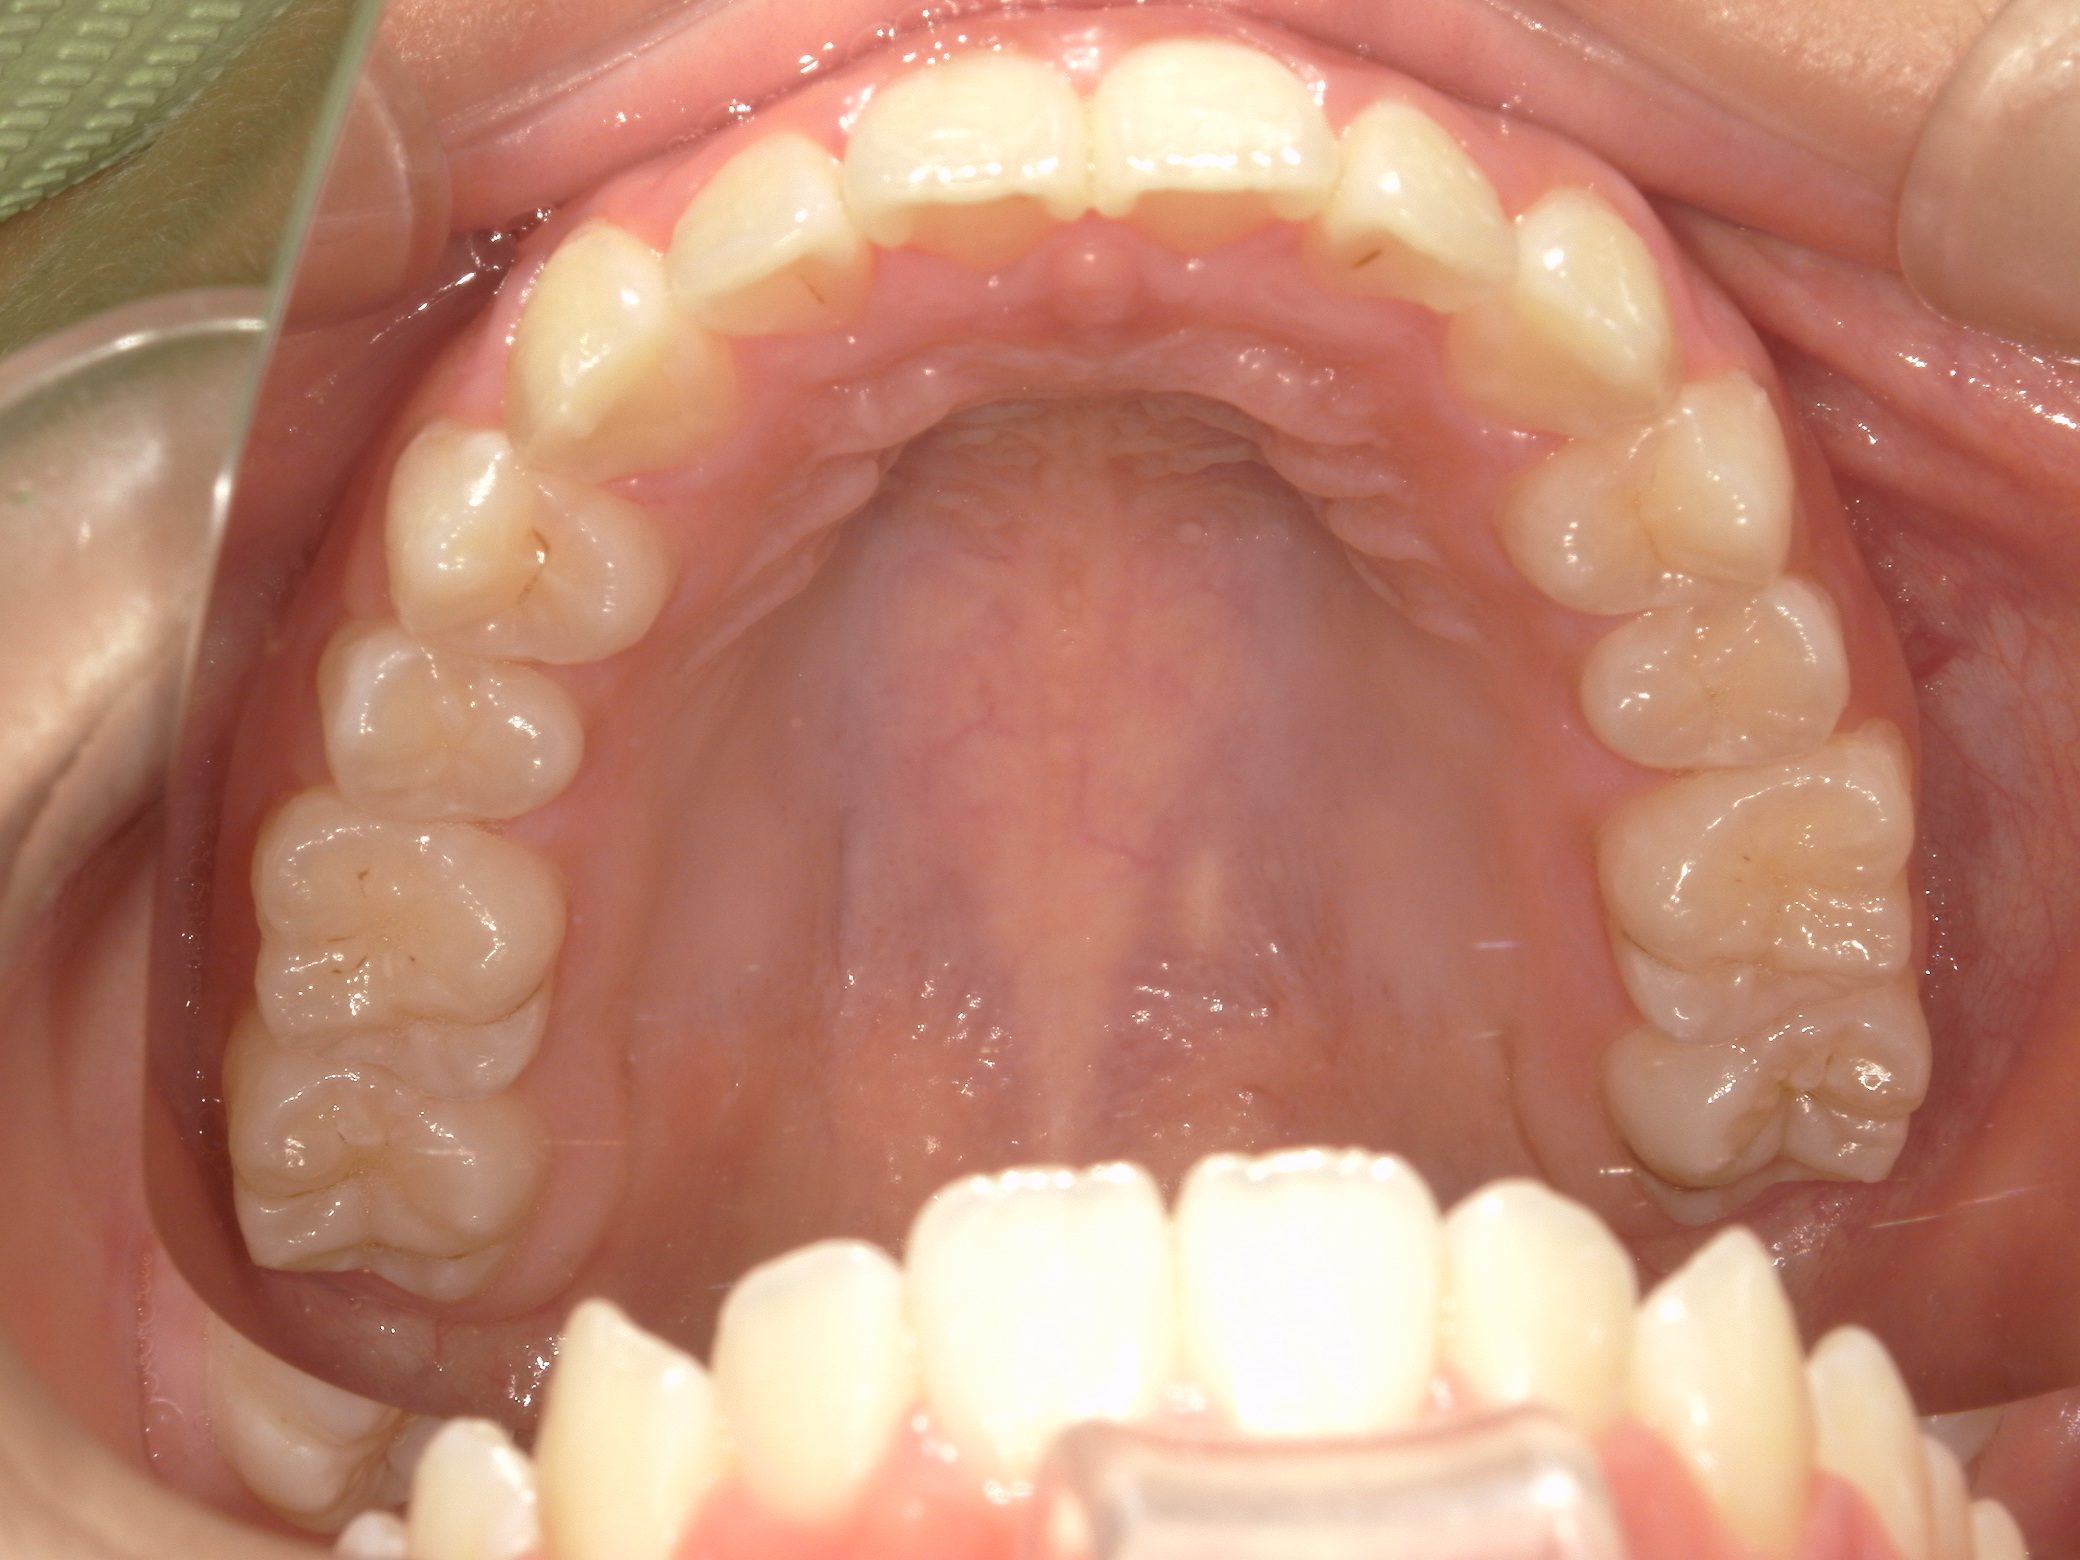

Before

After

【小学生】マイオブレース矯正➡ 【中学生】インビザラインフル 受け口 と 開咬 を改善

1期治療で 機能矯正装置と MFT 2年

2期治療でインビザラインフル 2年 をした患者さんです

もともと 舌癖があって 開咬 と 受け口の傾向があり

小児矯正(1期治療)をしましたが、咬み合わせに惜しいところがあり、2期治療まで行いました。

最終的に非常に良い咬み合わせになりました。